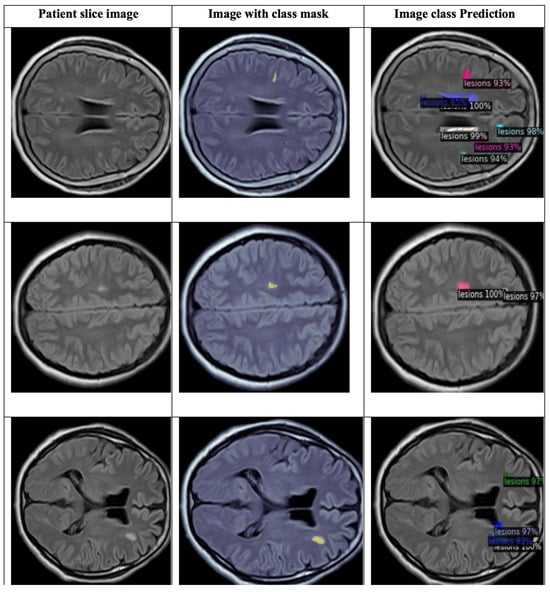

4.2.3. YOLO Model for Detecting WMH Lesions

- The curves of “train/box_loss” and “val/box_loss” show the training and validation loss related to the bounding box predictions. As the loss function decreases, it signifies that the network is effectively learning and enhancing its capability to precisely predict well-fitted bounding boxes.

- The “train/seg_loss” and “val/seg_loss” represents the training and validation segmentation loss.

- The “train/cls_loss” and “val/cls_loss” refer to training classification loss, which evaluates the classification accuracy of each predicted bounding box.

- The “train/dfl_loss” and “val/dfl_loss” indicate the training distribution focal loss, indicating the model’s confidence in predictions.

- The graph of “metrics/precision(B)” and “metrics/precision(M)” indicates the precision for bounding box predictions and precision for mask predictions, respectively.

- The “metrics/recall(B)” and “metrics/recall(M)” are the recall for bounding box predictions and recall for mask predictions, respectively. This indicates the ability to identify true positive masks.

- The “metrics/mAP50(B)” and “metrics/mAP50(M)” are the mean average precision at 50% IoU (Intersection over Union) for bounding boxes and for masks, respectively.

- The “metrics/mAP50-95(B)” and “metrics/mAP50-95(M)” are the mean average precision at IoU thresholds from 50% to 95% for bounding boxes and for masks, respectively.